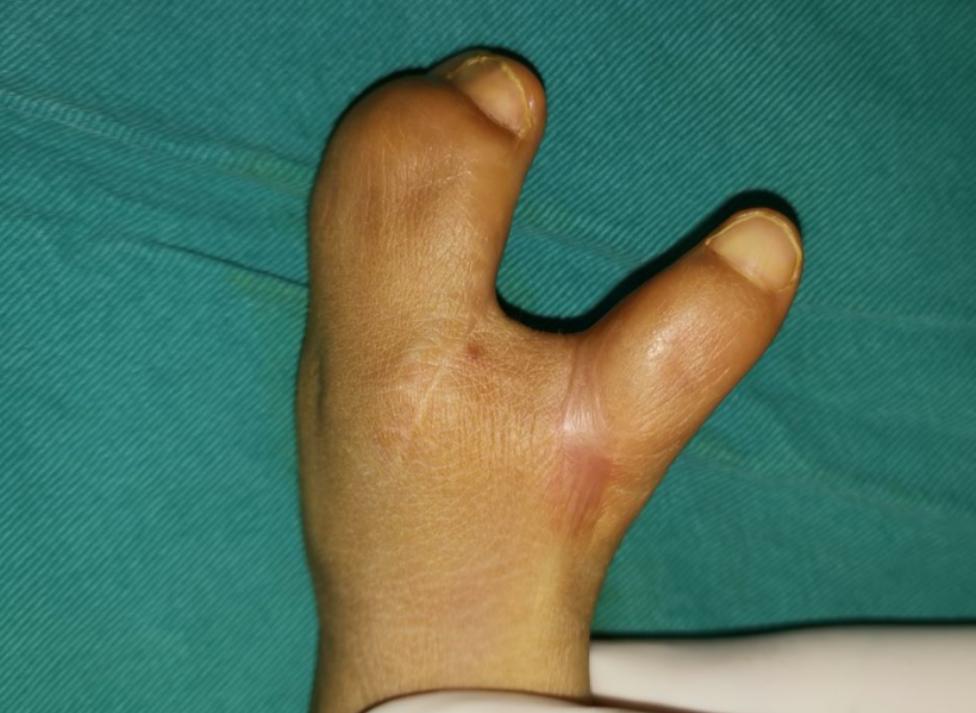

病例10是Apert综合征的孩子,Apert综合征又称为尖头并指综合征。对于这种类型的孩子来说,我们最重要的目标是让孩子有一个拇指,因为拇指占据了手部50%的功能,没有拇指很多事情都做不了,把拇指分出来之后,孩子就可以做捏、夹、拧瓶盖等动作。长大之后我们又给孩子分出来两根手指,这样孩子手的功能就逐渐地建立完善起来了。